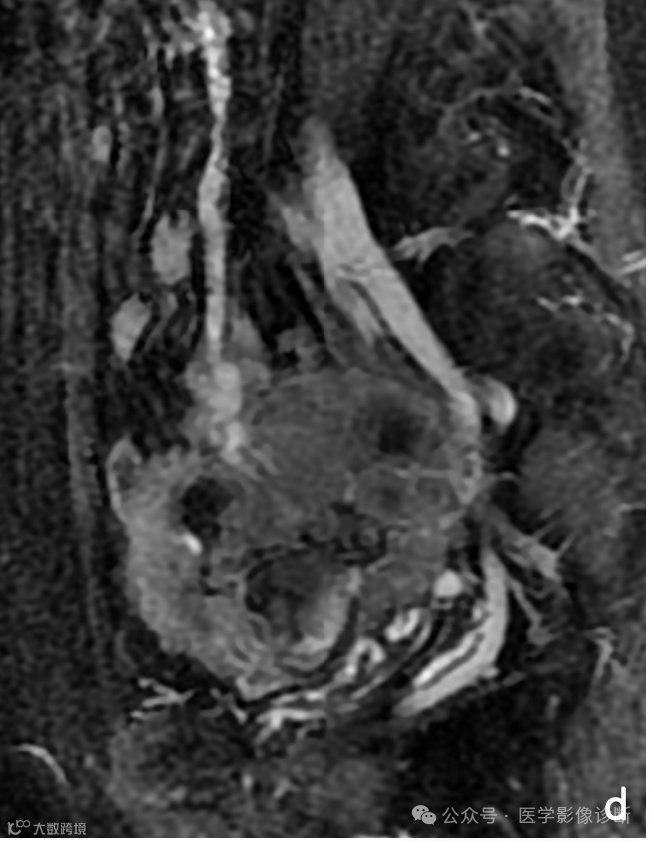

患者,女性,57岁,盆腔肿物就诊于妇科,妇科医生诊断为卵巢肿瘤。

MRI扫描(a - c)显示盆腔肿块,T1WI呈出血样高信号,T2WI/FS内部呈低信号。增强扫描表示非均匀增强。肿块与小肠密切相关,增强MRI矢状面(d)和轴向CT (e)可见肠系膜大血管(箭头)供血,提示肠道原发病变。然而放射科医生受临床卵巢肿瘤的诊断干扰未能明确诊断为小肠间质瘤。